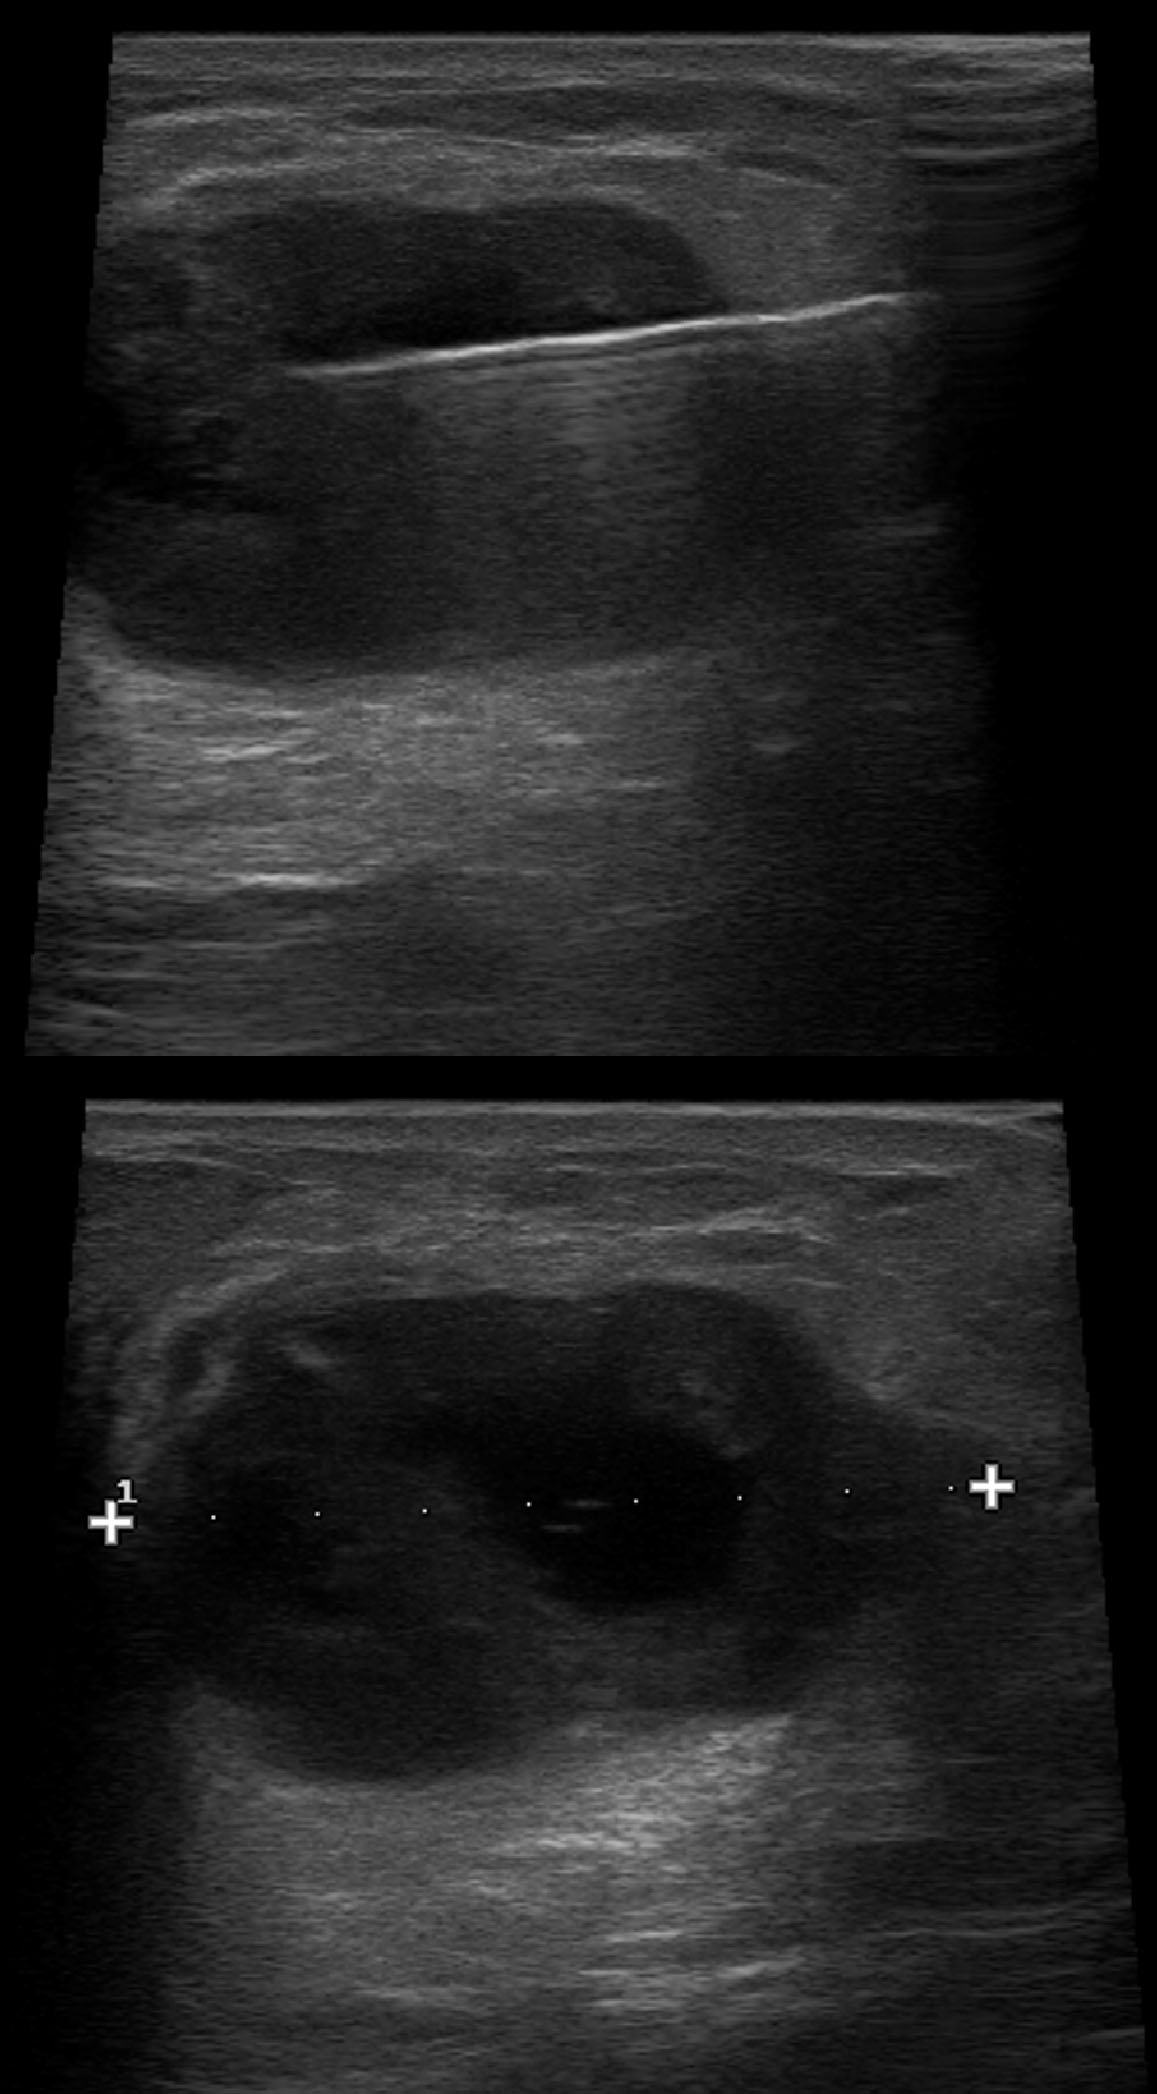

Dr. Alberto Gallardo (patòleg) i Dra. Ferrer (radiòleg).

Clínica Girona

Paciente varón de 54 años con tumoración en unión de cuadrantes superiores de mama izquierda que parece depender del músculo. Se realiza punción con aguja fina.

Se adjunta fotografías de las extensiones, bloque celular y mamografía y ecografía.

Dra. Mª Jesus Diaz Ruiz (radiòloga) i Dra. Carme Vergara Larrosa (Patòloga).

Althaia, xarxa assistencial universitària de Manresa

Dona de 50 anys, en cribatje de mama des dels 40; assimtomàtica. En una de les mamografies es troben calcificacions en QIE de mama esquerra de nova aparció.

En els controls succesius aparició de tumoració en QIE mama esquerra amb traducció radiològica de quist complicat de 13mm.

Es realitza PAAF: el diagnòstic es de abundant cel·lularitat inflamatoria, negatiu per cèl·lules malignes. Material citològic compatible amb quist.